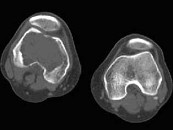

- 男,40岁, 慢性左膝痛,结合图像, 最